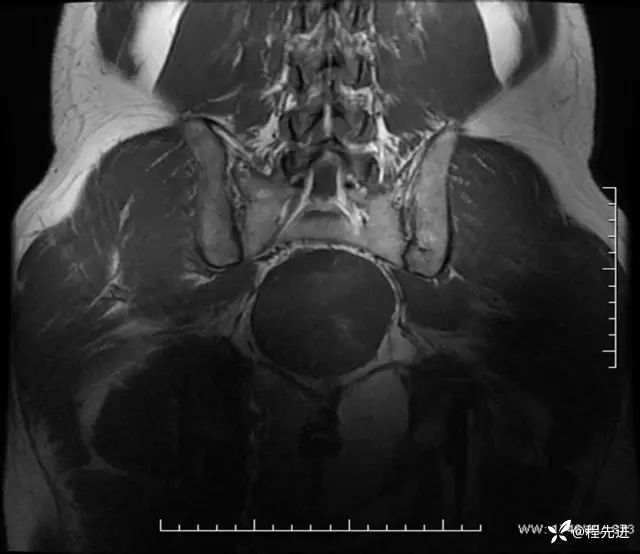

T1冠状位: